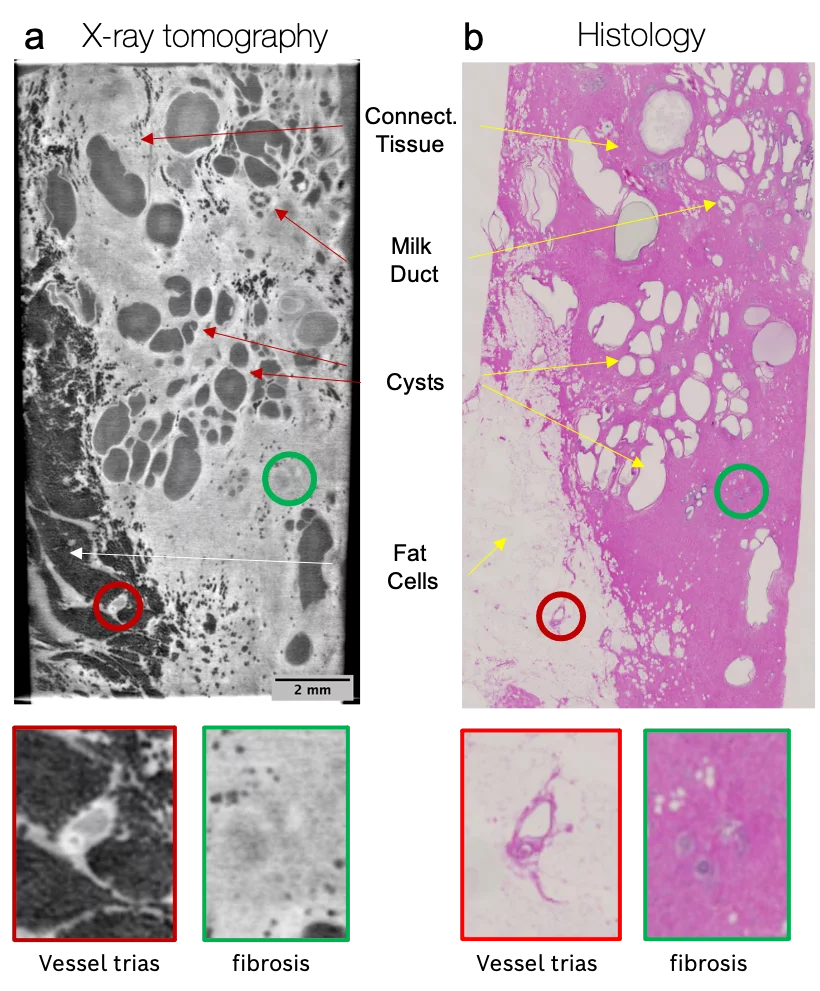

Exploiting the higher sensitivity of X-ray phase contrast is particularly suited for biological soft tissues. Therefore, the proposed approach may substantially reduce the staining requirements of the specimens, thus allowing their examination in conditions closer to their natural state. In addition, X-ray microtomography does not destroy the tissue as the sectioning is virtually done a posteriori on its three-dimensional tomographic image reconstruction.

In our team, a prototype of the new X-ray uCT setup was assembled. Based on the grating interferometry, the system provides high spatial resolution (<10 µm) and field of view (up to 2.0 cm). Therefore, the three-dimensional information obtained from X-ray phase-contrast microtomography nicely corresponds to the images obtained by conventional histological techniques.